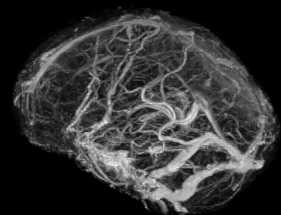

El cerebro posee un sistema de venas cerebrales, las cuales se clasifican en un grupo superficial y otro profundo, y un sistema de senos venosos,  los de la base y los senos intermedios. Todos ellos van a drenar finalmente en la vena yugular interna que emerge de la base del cr�neo y desciende formando el paquete vasculonervioso cervical.

El grupo superficial drena la corteza y la sustancia blanca subcortical, desembocando en los senos sagital superior o en los senos de la base.

El grupo profundo drena el plexo coroideo, las regiones periventriculares, el dienc�falo (talamo e hipotalamo), los n�cleos basales y la sustancia blanca profunda; desemboca principalmente en las venas cerebrales internas y en la Vena de Galeno o Cerebral Mayor

Venograma cerebral comparese con figura superior